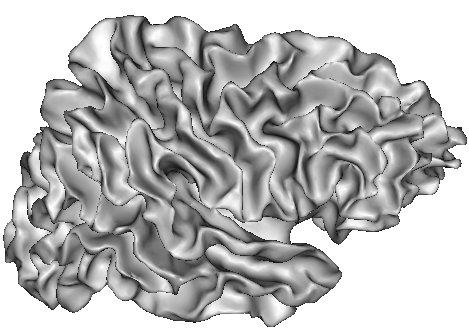

Imagine that a cerebral hemisphere has been split in two, and that white matter has been removed. The cortical surface can then be visualised from the inside:

This point of view helps to understand he skeletonization effect:

The skeleton is made up of the the brain hull and of the numerous surfaces medial to the folds: